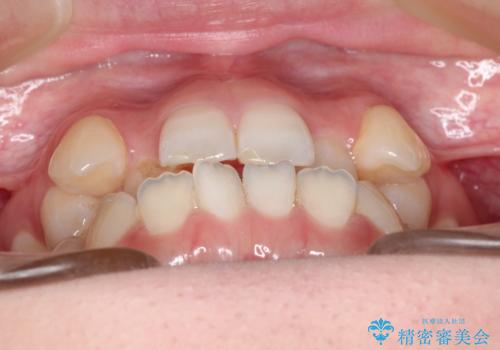

MARPEで非抜歯矯正|オープンバイトと八重歯を改善

- 治療計画

上顎にTAD(矯正用アンカースクリュー)を設置し、MARPEにより骨格レベルで上顎の幅を拡大。数週間の拡大期間を経て十分なスペースを確保したのち、マウスピース型矯正装置(インビザライン)で歯列全体を整えました。八重歯もアーチ内に自然に収まり、非抜歯で審美性と機能性を両立。治療後は「噛み合わせが安定して笑顔に自信が持てるようになった」とご本人にも大変満足していただきました。